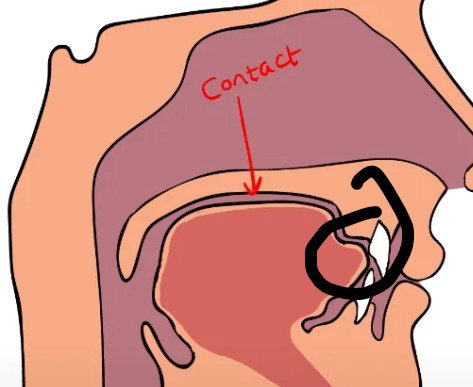

yes, or you might just have a huge tongue since you say it feels like ur palate is narrow, even though its wideif my tounge touches the front of my teeth when resting it, is it because my maxilla is not forwardly grown enough?

if my tounge touches the front of my teeth when resting it, is it because my maxilla is not forwardly grown enough?wide

yes, or you might just have a huge tongue since you say it feels like ur palate is narrow, even though its wideif my tounge touches the front of my teeth when resting it, is it because my maxilla is not forwardly grown enough?